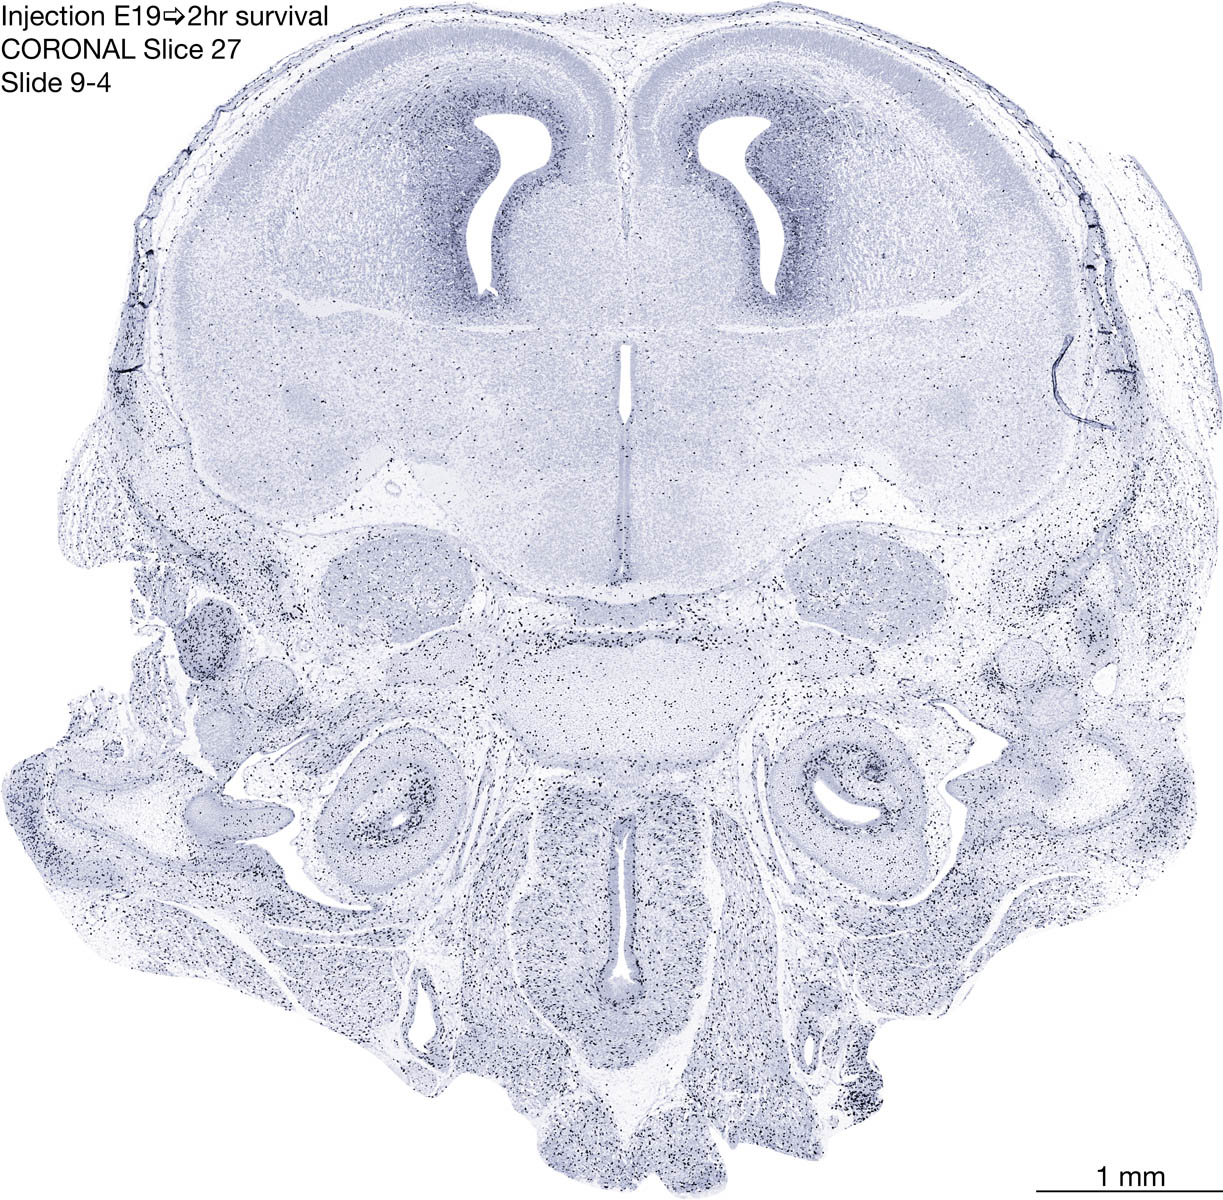

E19 2hr Survival Archived Images-Coronal The following images are from a paraffin-embedded coronally-sectioned head of an E19 rat embryo exposed to tritiated thymidine 2 hours before death. Download: Large | High Res Download: Large | High Res Download: Large | High Res Download: Large | High Res Download: Large | High Res Download: Large | High Res Download: Large | High Res Download: Large | High Res Download: Large | High Res Download: Large | High Res Download: Large | High Res Download: Large | High Res Download: Large | High Res Download: Large | High Res Download: Large | High Res Download: Large | High Res Download: Large | High Res Download: Large | High Res Download: Large | High Res Download: Large | High Res Download: Large | High Res Download: Large | High Res Download: Large | High Res Download: Large | High Res Download: Large | High Res Download: Large | High Res Download: Large | High Res Download: Large | High Res Download: Large | High Res Download: Large | High Res Download: Large | High Res Download: Large | High Res Download: Large | High Res Download: Large | High Res Download: Large | High Res Download: Large | High Res Download: Large | High Res Download: Large | High Res Download: Large | High Res Download: Large | High Res Download: Large | High Res Download: Large | High Res Download: Large | High Res Download: Large | High Res Download: Large | High Res Download: Large | High Res Download: Large | High Res Download: Large | High Res Download: Large | High Res Download: Large | High Res Download: Large | High Res Download: Large | High Res Download: Large | High Res Download: Large | High Res Download: Large | High Res Download: Large | High Res Download: Large | High Res Download: Large | High Res Download: Large | High Res Download: Large | High Res Download: Large | High Res Download: Large | High Res Download: Large | High Res Download: Large | High Res Download: Large | High Res Download: Large | High Res Download: Large | High Res Download: Large | High Res Download: Large | High Res Download: Large | High Res Download: Large | High Res Download: Large | High Res Download: Large | High Res Download: Large | High Res Download: Large | High Res Download: Large | High Res Download: Large | High Res Download: Large | High Res Download: Large | High Res Download: Large | High Res Download: Large | High Res Download: Large | High Res Download: Large | High Res Download: Large | High Res Download: Large | High Res Download: Large | High Res Download: Large | High Res Download: Large | High Res Download: Large | High Res Download: Large | High Res